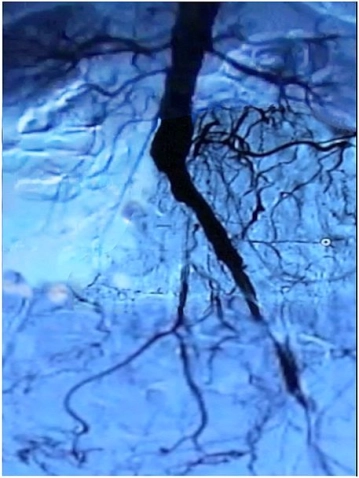

Ejemplo de película:

Präoperatives Angiogramm

El paciente presenta clínicamente una PAVK IIb - III según Fontaine, la angiografía preoperatoria muestra: oclusión de la A. iliaca communis et externa der., estenosis subtotal de la A. iliaca externa izq. incl. estenosis de la bifurcación femoral bilateral.

-> TASC D, por lo tanto, recomendación para reconstrucción abierta